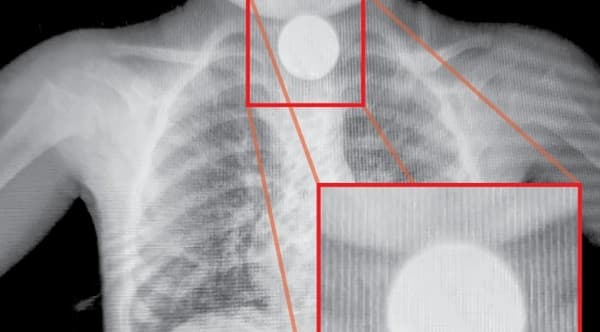

La beba, de 27 semanas de gestación y con un peso de 450 gramos, había nacido el viernes 12 de abril en el Hospital Regional de Ciudad del Este sin presentar signos vitales. Fue declarada fallecida y entregada a sus familiares, pero media hora antes del sepelio, un tío notó que se movía en su ataúd.